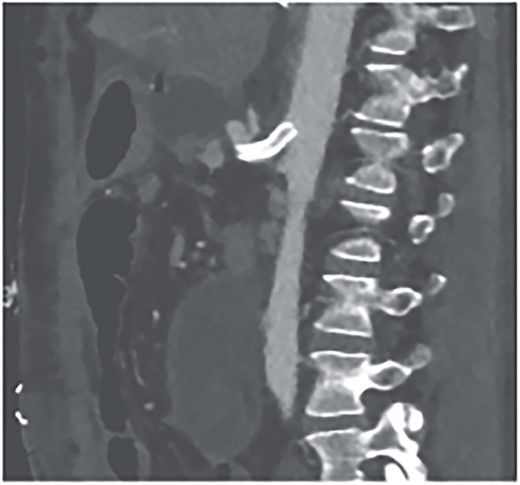

Postoperatively, the patient achieved hemodynamic stabilization in the intensive care unit. On the sixth postoperative day, there was a recurrence of circulatory collapse in addition to relevant bloody discharge through the drains. CT imaging once again revealed an active bleeding of the pancreaticoduodenal artery, which was successfully treated interventionally using coiling (Figs 2 and 3).

Postinterventional angiography, showing the aneurysm of the pancreaticoduodenal arcade, after interventional coiling.